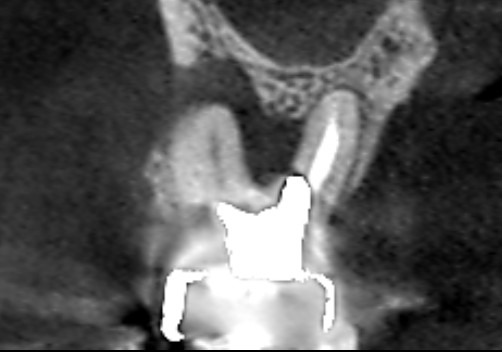

初診時の第一大臼歯の冠状断のCT画像です。

第一大臼歯の冠状断CT画像の赤い矢印の先の膿は、青い矢印の先で起きているメタルコアによる根管壁穿孔(パーフォレーション)によるものと考えられます。